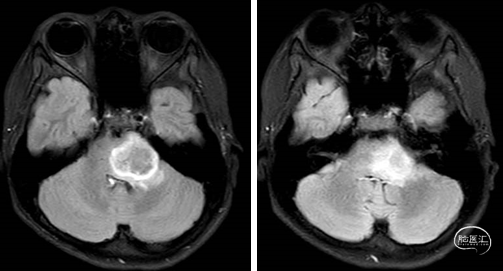

现病史:患者半年前无明显诱因下自觉头痛,主要为双颞侧,性质胀痛,不剧可忍,偶有恶心呕吐,呕吐物为胃内容物,当时未予重视及治疗。10天前,患者自觉头痛加重,每次持续约1-2分钟,每日约有3-4次,伴恶心呕吐,伴右下肢乏力感。2023-09-12家属急送至曹县人民医院就诊,行头颅CT提示:疑左侧桥脑旁肿瘤。患者家属为求进一步诊治,至我院门诊,(2023-09-14 08:50)行头颅平扫加增强扫描(3.0T)检查提示:桥脑、左侧桥臂占位,高级别胶质瘤可能大。门诊拟“脑干肿瘤”收住入院。

目前诊断:脑肿瘤(左侧桥脑)。